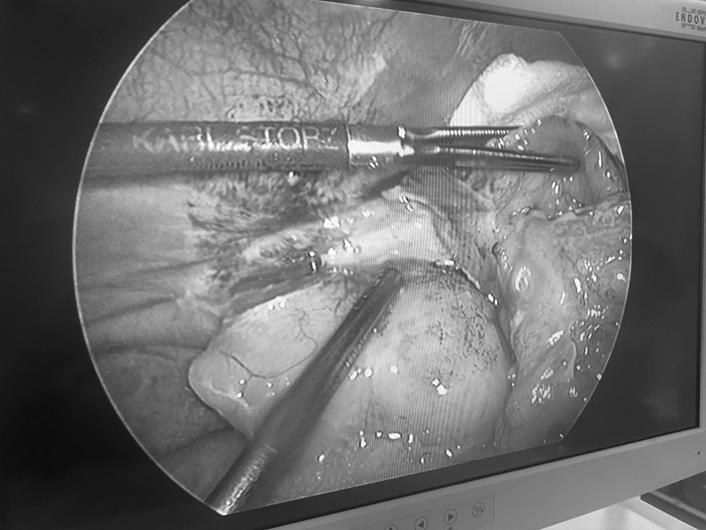

Trong quá trình phẫu thuật làm sạch hố chậu phải, bác sĩ phát hiện túi thừa manh tràng của bệnh nhân bị thủng với một lỗ kích thước khoảng 5mm kèm khối dịch và phân tụ lại tại hố chậu phải. Bệnh nhân sau đó đã được phẫu thuật cắt bỏ túi thừa, làm sạch ổ bụng và khâu lổ thủng túi thừa manh tràng nội soi, chuyển phòng hồi sức sau mổ để được điều trị tích cực, dùng kháng sinh mạnh. Đến nay, bệnh nhân đã hồi phục tốt và được xuất viện.

Hình ảnh túi thừa manh tràng bị thủng qua phim nội soi